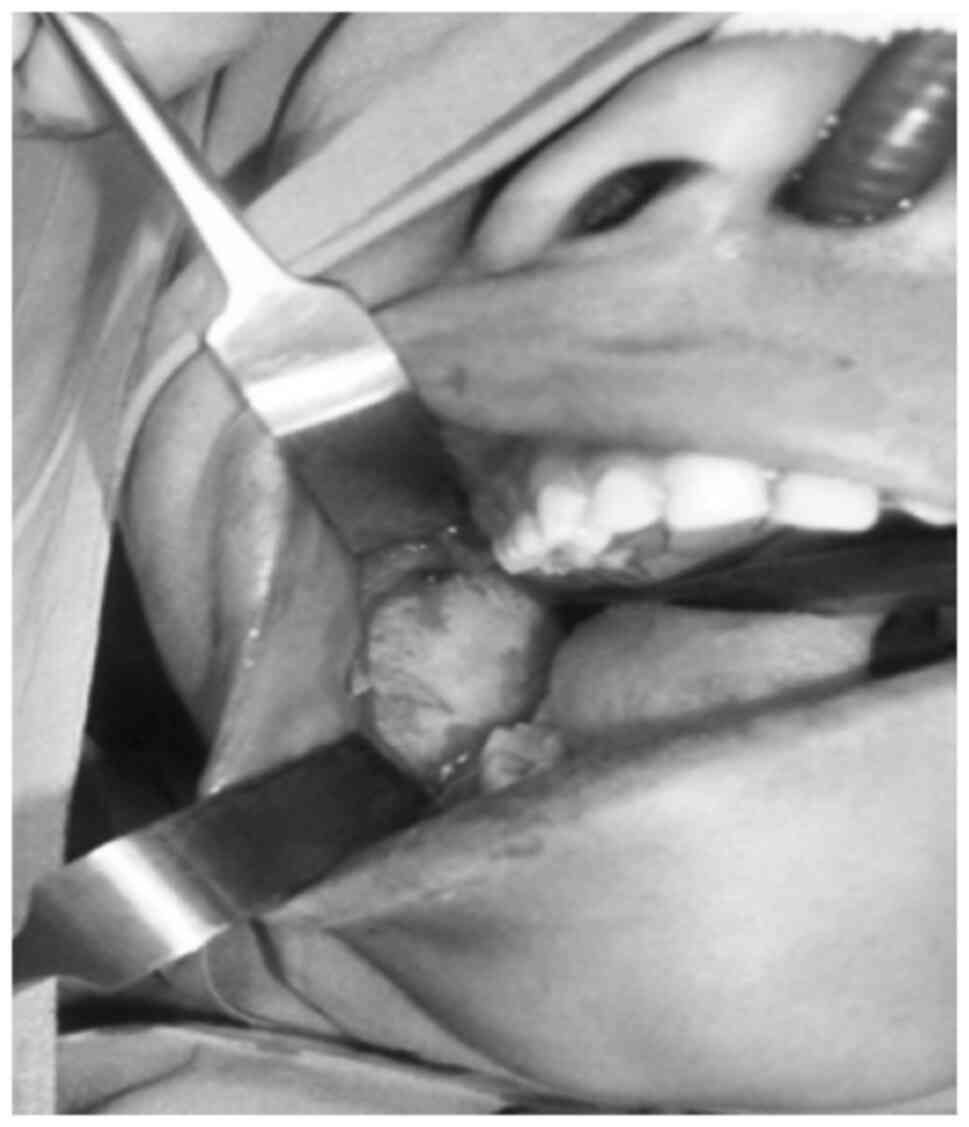

The final diagnosis of the tumor was AFO. The soft tissue healing process was uneventful, with no evidence of recurrence during the 2-year follow-up period (Fig. 4).

Figure 4

Post-operative evaluation of the site of the lesion (arrowhead), illustrating uneventful healing after 1 year.